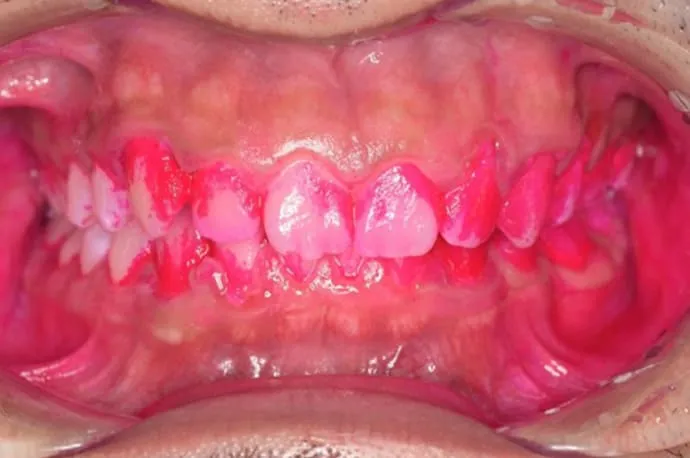

治療前

治療後

こちらの画像は、ブラッシング前後の染め出しの画像です。汚れがついている部位は濃くピンクに染まります。1回の歯磨き指導でも、汚れの付着が大きく減っていることが確認できます。ぜひ一度、高輪の歯医者「TAKANAWA GATEWAY Clinics 歯科・矯正歯科」へご来院いただき、自己流の歯磨きから卒業してみませんか?